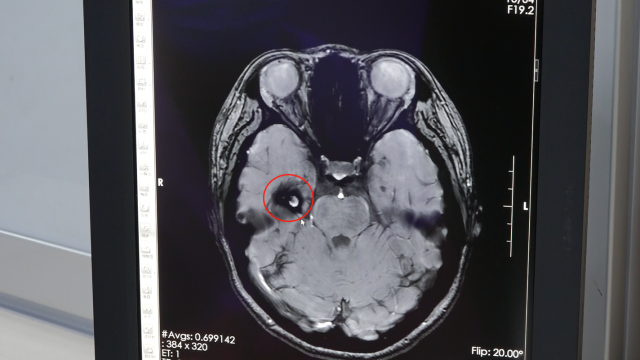

影像检查提示右侧颞叶占位性病变。 受访者供图

完善相关检查后,7月5日,吾太华采取锁孔入路的方式为患者行右侧颞叶占位性病变切除术。术中切除大小约1.5cm×1cm×1cm的畸形血管团,并将周围含铁血黄素沉着区组织全部吸除。“手术切口3-4cm,比传统手术创伤小。”吾太华补充道。